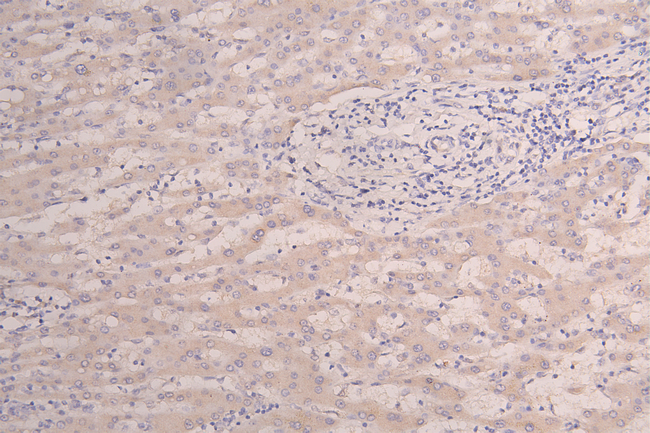

IHC image of CSB-RA010327MA1HU diluted at 1:100 and staining in paraffin-embedded human Liver tissue performed on a Leica BondTM system. After dewaxing and hydration, antigen retrieval was mediated by high pressure in a citrate buffer (pH 6.0). Section was blocked with 10% normal goat serum 30min at RT. Then primary antibody (1% BSA) was incubated at 4°C overnight. The primary is detected by a Goat anti-Human IgG labeled by HRP and visualized using 0.05% DAB.